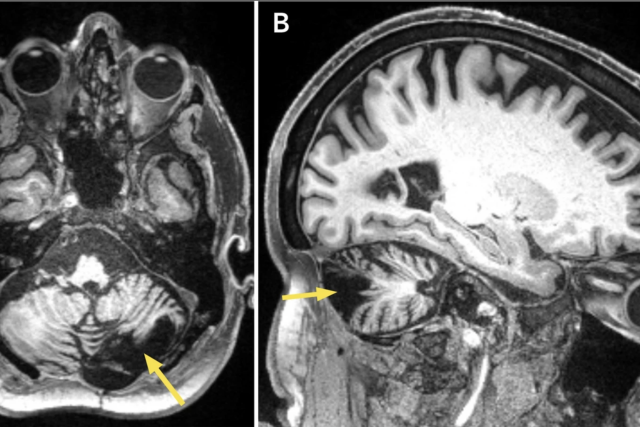

Brain MRI of post-stroke cerebellar lesion.

MRI brain of post-stroke cerebellar lesion